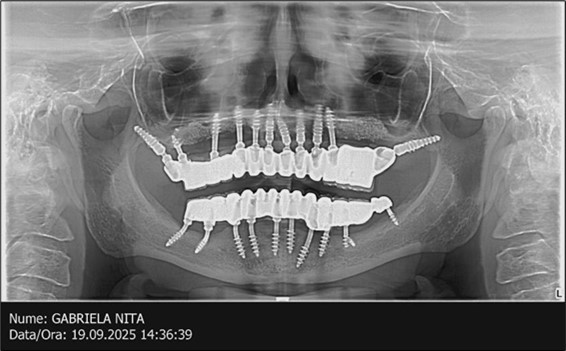

Figure 15.Follow-up panoramic X-ray 09.2025

Follow-up panoramic X-ray 09.2025

The results of rehabilitation treatment with corticobasal and compressive implants with a polished surface after the failure of two stage implants were highlighted over a period of 3 years and 3 months as being very good (Figure 14, Figure 15), with the patient completing a satisfaction survey in this regard. Certainly, it is necessary to continuemonitoring these results in the long term.